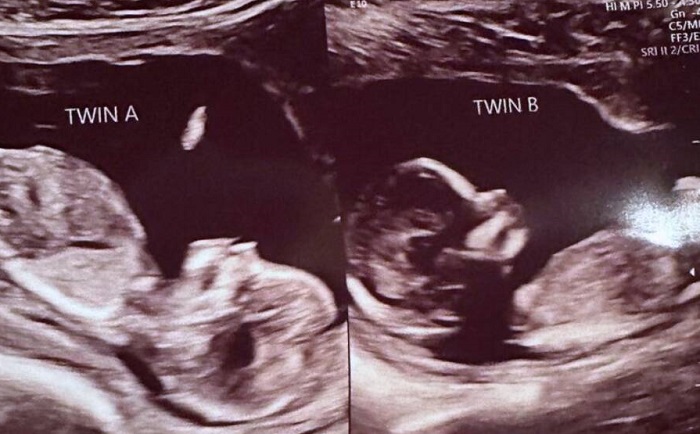

Dia terkejut ketika USG pertamanya menunjukkan dua janin yang sedang tumbuh, satu di setiap rahim.

Secara ilmiah, kehamilan tersebut terjadi secara terpisah, meskipun tim medis Hatcher memperlakukan bayi-bayi tersebut seolah-olah mereka adalah saudara kembar.

Menurut Patel, kedua indung telur Hatcher berovulasi dan melepaskan sel telur pada waktu yang hampir bersamaan, dan ini merupakan peristiwa yang jarang terjadi.

Kedua sel telur tersebut kemudian dibuahi, dan satu sel telur ditanamkan di setiap rahim.

"Saya pikir secara medis, ini adalah hal yang langka sehingga kita tidak punya cara yang lebih baik untuk menggambarkannya selain tetap menyebut mereka kembar," kata Patel.